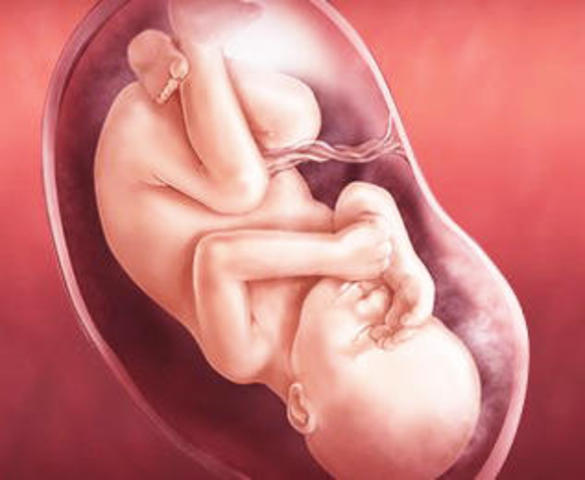

• SEMANA 30 A 34

SEMANA 30 A 34

Se observa el reflejo pupilar. La piel sigue con su coloración rosa. Las extremidades son más anchas. Ahora el tejido adiposo blanco constituye el 8% del peso corporal.